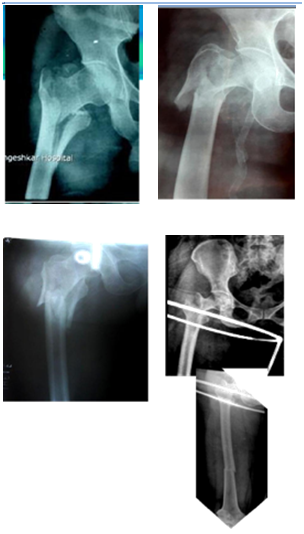

Preoperative plan

1. Study Head size/Neck size to see whether it will accommodate 2 screws.

2. Study Neck Shaft angle on opposite hip. Too much varus may make it unsuitable (Figure 4).

3. In case of failure to get closed reduction or in case of failure to obtain good valgus angle of head and neck proceed to open reduction or switch to DHS. Only 2 angles are available in PFN 130 and 135 degrees.

4. Back up option of DHS/ DCS/Extra long plate/TSP to be ready.

Figure 4 Beware of Varus. So common in Indians.